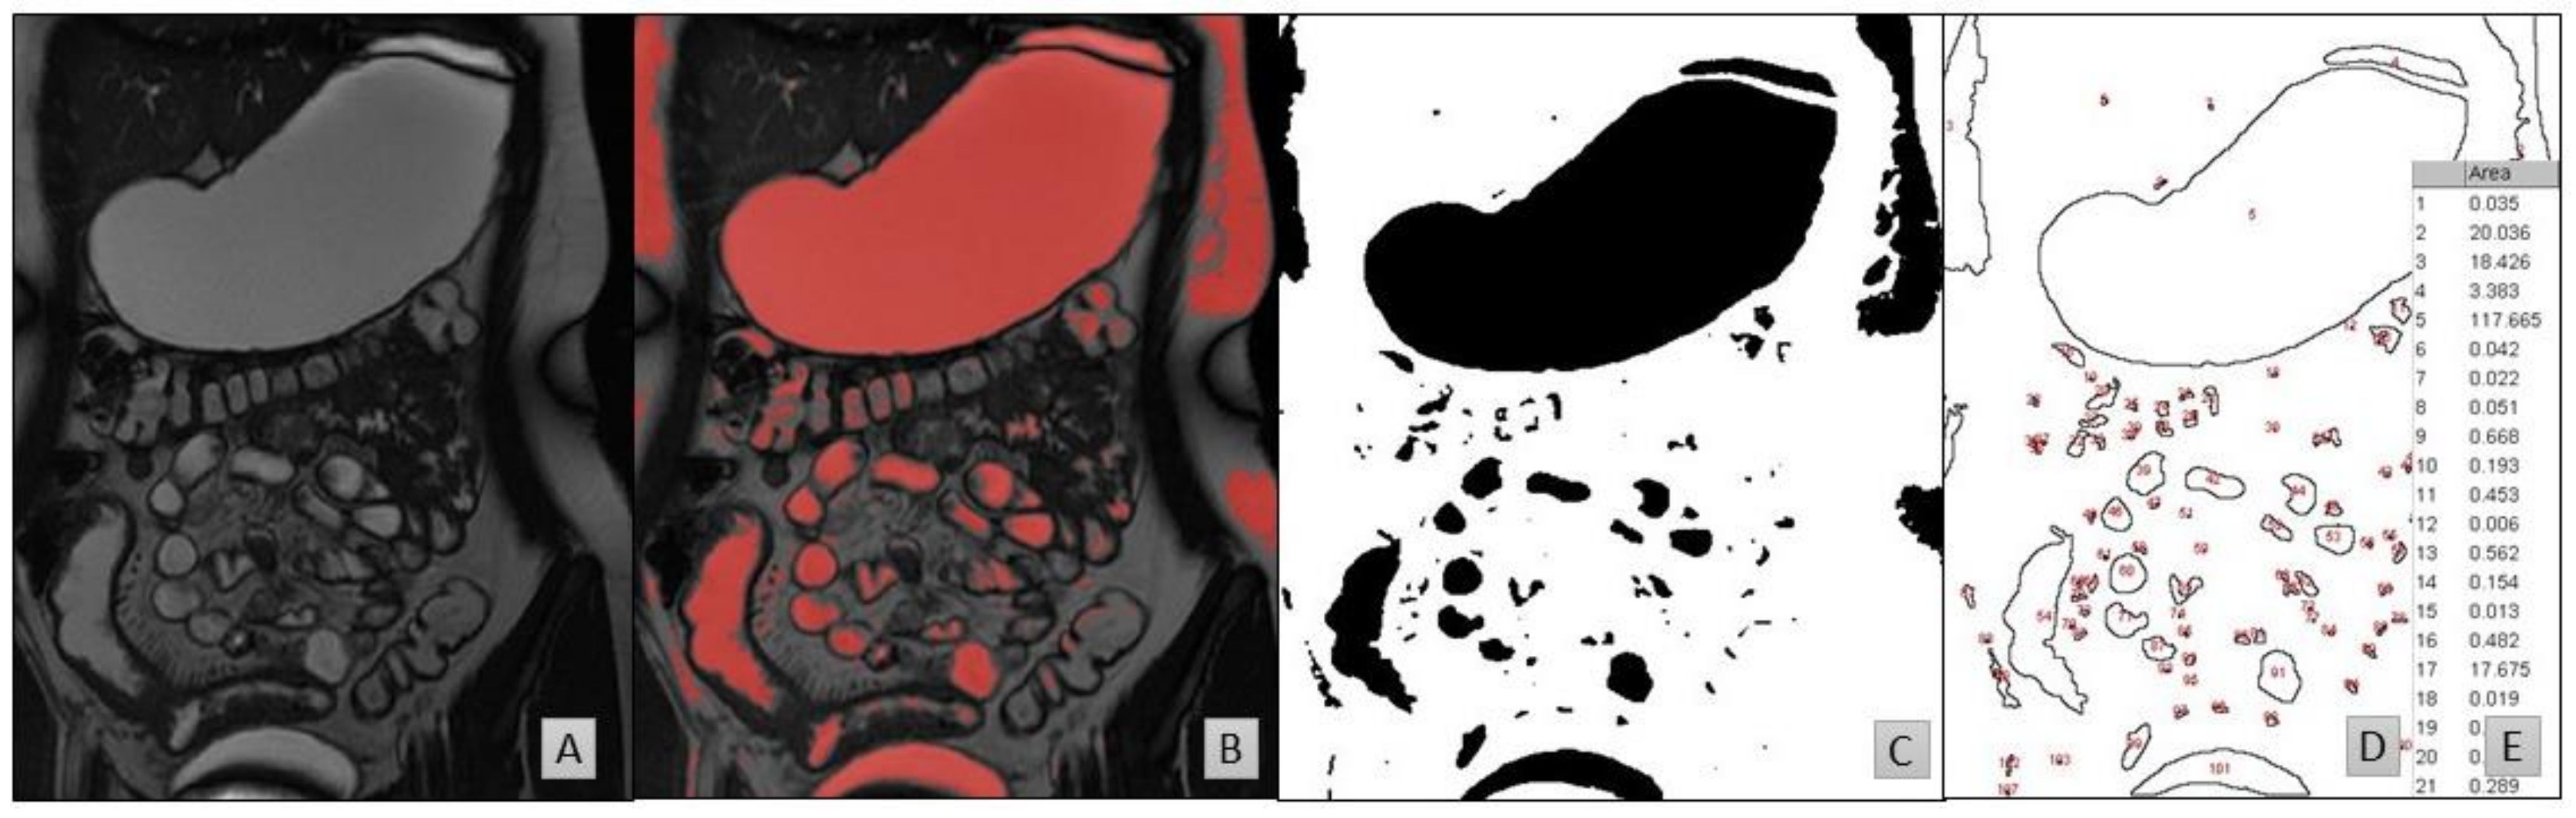

2.2. Data Processing

2.2.1. D-Protocol

- Horos [44] to identify and highlight the fluid pockets in the MRI dataset;

- ImageJ to calculate the area of the marked fluid regions.

2.2.2. Three-Dimensional Protocol

- Horos to identify and highlight the fluid pockets in the MRI dataset;

- Blender to remove artefacts and isolate and compute the fluid pockets.